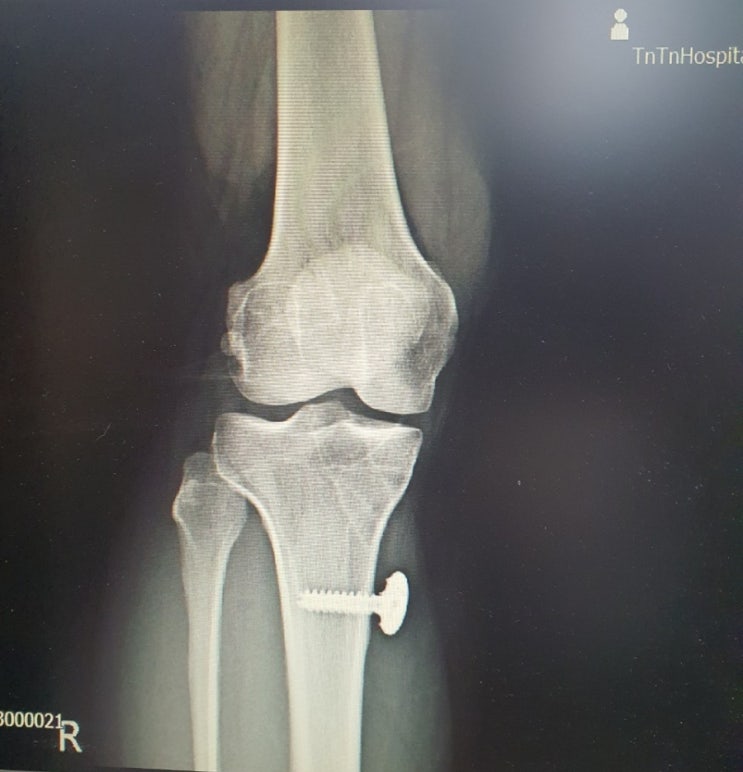

무릎 전방십자인대 파열 & 수술 & 재활, 그리고 2년된 지금의 일기

무릎 전방십자인대 파열 & 수술 & 재활, 그리고 2년된 지금의 일기 시작은 이러했다. 언니가 골때...